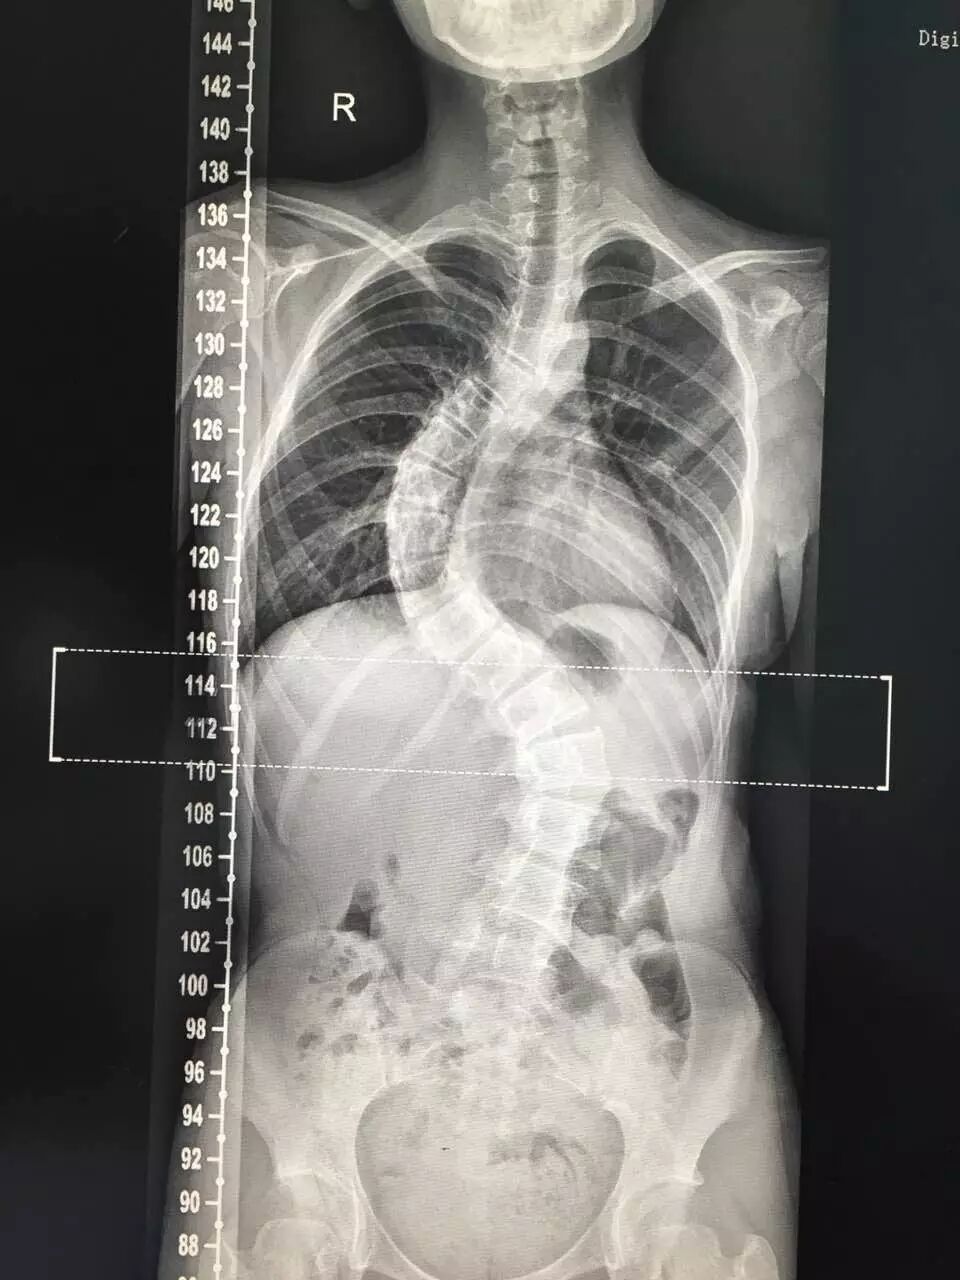

x光片图片全身